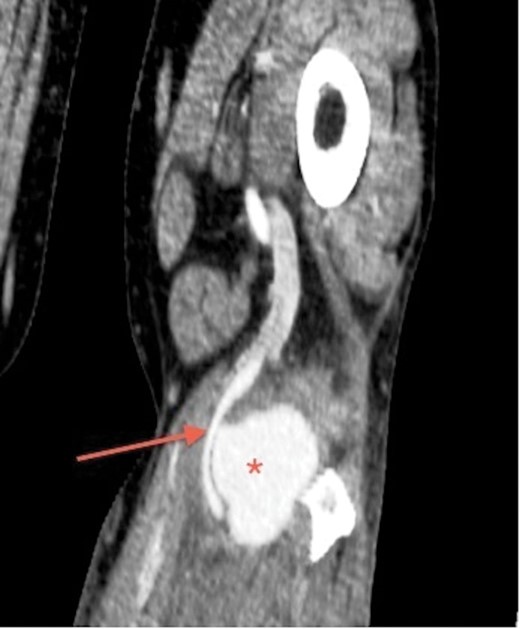

His laboratory reports for full blood count, urea and electrolytes were normal. In view of the ultrasound findings, a CT angiogram of lower limbs was performed. It confirmed 6 × 5 × 4 cm pseudoaneurysm, compressing and displacing his left popliteal artery. However, three-vessel run-off below the knee was satisfactory (Figs 1 and2).

CT angiogram of the left leg, transverse section, shows popliteal pseudoaneurysm (asterisk) adjacent to the popliteal artery (arrow).